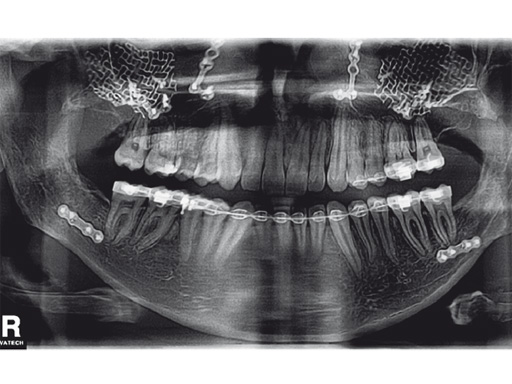

Case 2: A 19-year-old woman had an extended sinunasal carcinoma in the right maxillary sinus area. fig 2 shows four views of the virtual preplanned computer-aided design; the reconstruction is represented in pink (fig 2a). The three remaining multiplanar views show the overlapping images of the virtual preplanned reconstruction (pink) and reconstruction result performed by using two individualized 3-D meshes (one for a three-wall-reconstruction of the orbit and one for reconstructing the right midfacial prominences).